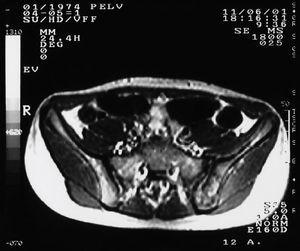

Se realizó analítica completa que incluyó hemograma, bioquímica con enzimas hepáticas, calcio, fósforo, fosfatasa alcalina, proteinograma, alfa-1-antitripsina, inmunoglobulinas y función renal, cuyos valores estuvieron dentro del rango de la normalidad. La velocidad de sedimentación globular (VSG) fue de 40 mm. La radiografía de tórax y la ecografía abdominal no evidenciaron alteraciones. En la radiografía de las sacroilíacas se observó una sacroilíaca izquierda con márgenes irregulares y mal definidos (fig. 1). En la gammagrafía con 99mTc se describió una lesión localizada en la sacroilíaca izquierda que deformaba y superaba esta articulación, con bordes abollonados hipercaptantes de forma moderada y áreas frías centrales. Se llevó a cabo una tomografía axial computarizada (TAC) de las sacroilíacas que puso de manifiesto alteraciones en la arquitectura trabecular del hueso ilíaco izquierdo con focos de lisis y esclerosis ósea adyacente a la articulación (fig. 2). En la resonancia magnética (RM) de las sacroilíacas se observaron cambios en la intensidad de la señal del componente medular de la pala ilíaca izquierda, con alternativa de hipo e hiperintensidad, y asimetría tenue de partes blandas con leve aumento de volumen en las zonas próximas al hueso sugestivo de proceso infiltrativo tumoral (fig. 3). En la TAC torácica se describió una imagen nodular en el lóbulo inferior izquierdo en los segmentos posteriores compatible con metástasis pulmonar. La biopsia de médula ósea no mostró signos de infiltración neoplásica. Se realizó una biopsia de la lesión que evidenció un tumor indiferenciado de célula redonda pequeña, con afección de hueso, periostio y músculo esquelético así como la presencia de fibrosis y desmoplasia estromal notables, sin signos de diferenciación. Los marcadores CD45, PAS, proteína S-100 y desmina fueron negativos. Se observó también manifiesta positividad de membrana para el anticuerpo CD-99 (O13), vimentina + + + y ENS (enolasa neuronal) + /-. Este patrón fue compatible morfológica, histoquímica e inmunocitoquímicamente con tumor de Ewing.

Figura 2. Tomografía axial computarizada (TAC) de sacroilíacas. Existen alteraciones en la arquitectura trabecular del hueso ilíaco izquierdo con focos de lisis y esclerosis ósea adyacente a la articulación.